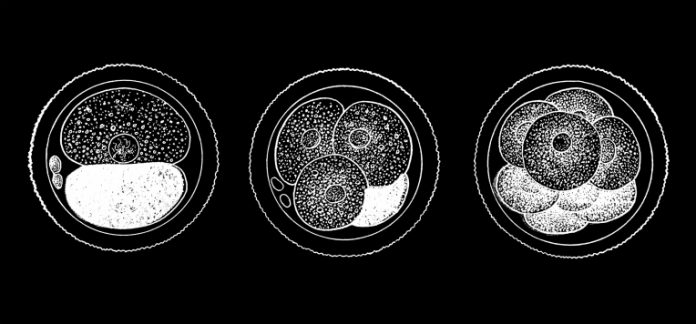

DIOLs first makes primordial germ cells, the source of sperm and oocytes. It differentiates between them to find oogonia, or the precursor of oocytes and then introduces genes into the iPS cells. This means that people who are dealing with infertility can potentially use DIOLs to have offspring with their own genetic material.

Dr. Hamazaki said that in the case of mice, it usually takes 30 days to get oocytes, and that with human oocytes, it can take up to six months.